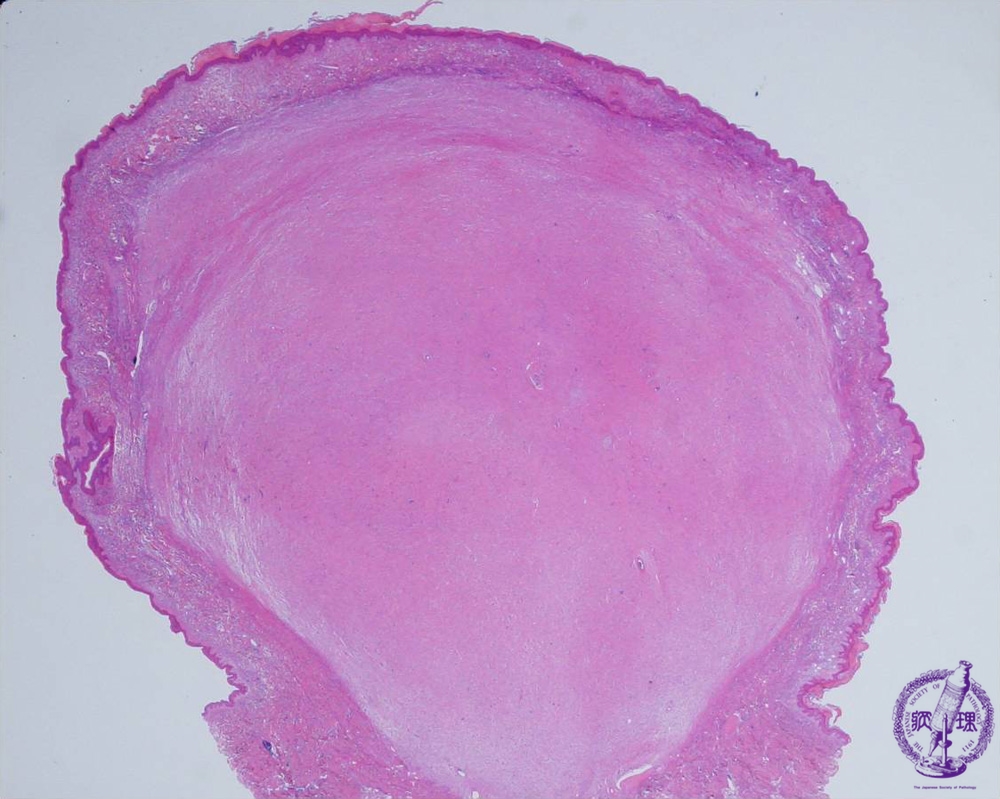

Microscopic findings: Tumor cells show diffuse proliferation. The tumor shows expansive growth and the border of the tumor is relatively clear. Sometimes skin appendages remain inside the tumor.